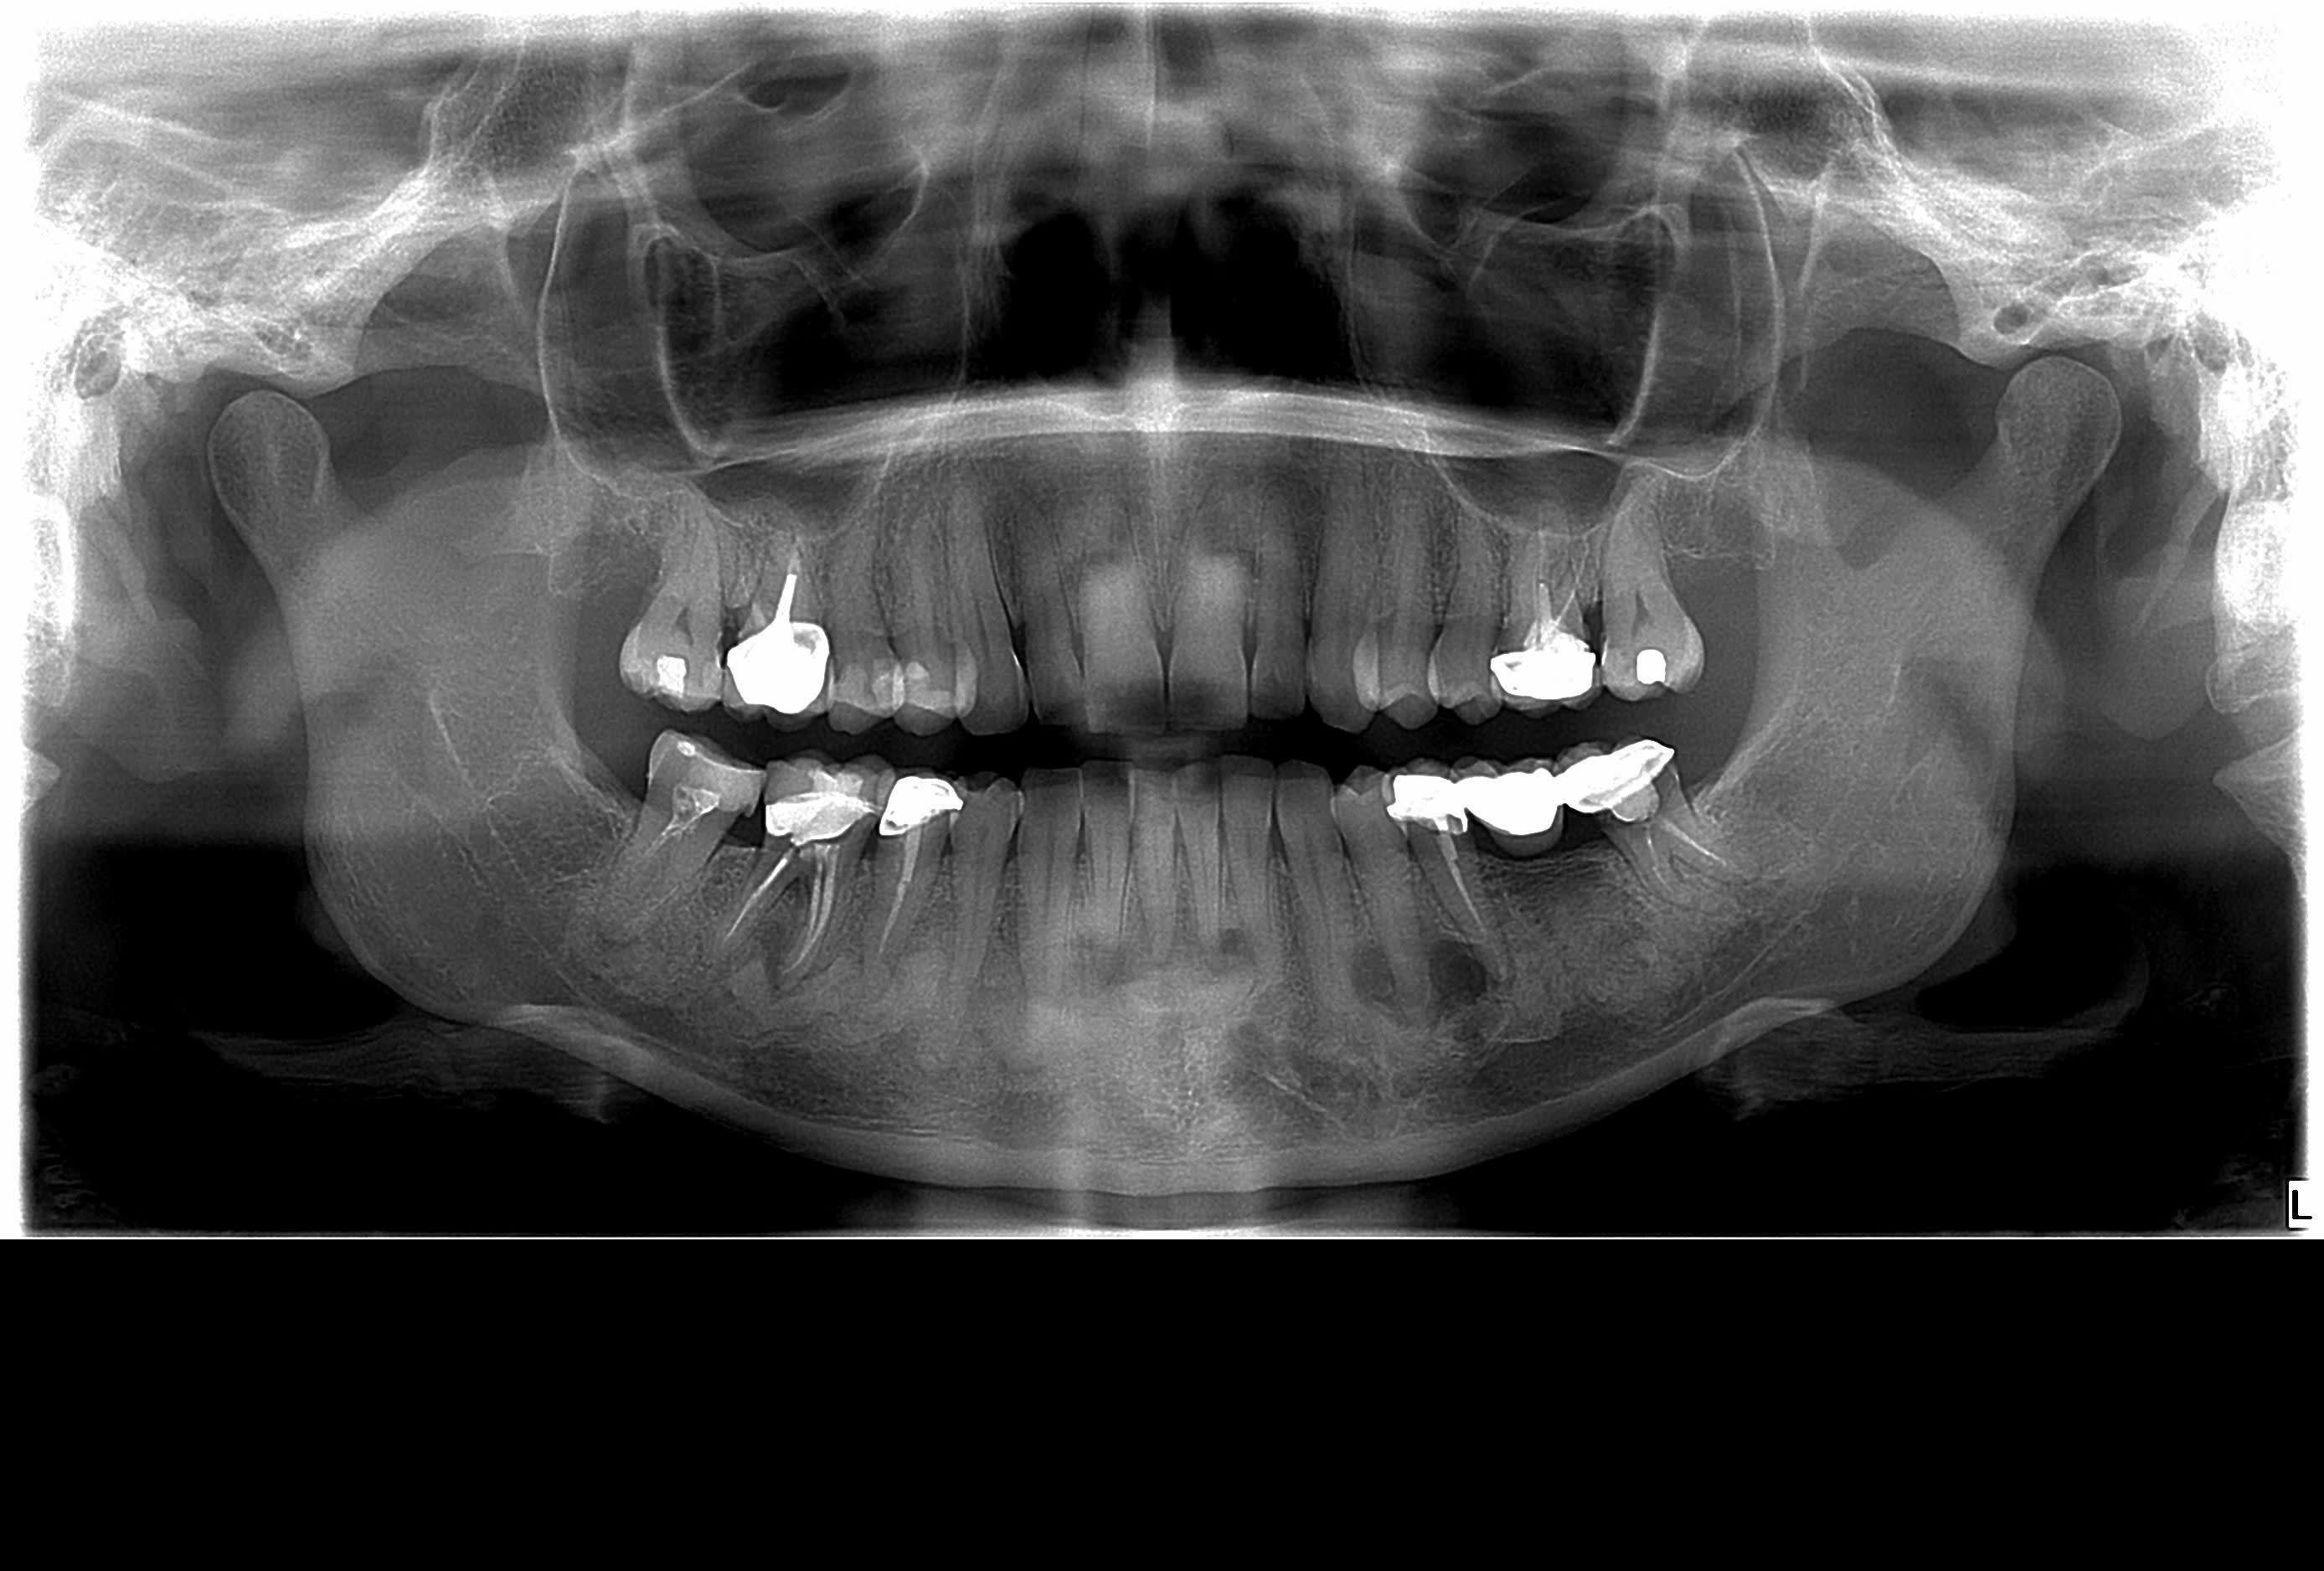

Sur un cbct on notes diverses lésions variées.

Terrain Paro avec de fait des surcharges occlusales sur les incisives, ça peut exacerber la réponse inflammatoire que l'on retrouve à l'apex des dents dévitalisées.

Certaines prémos ont aussi des débuts d’images radioclaires apicales, en tout cas c’est pas net. Elles sont également intactes et répondent normalement au froid.

Pour enlaye, ça n’est pas un problème d’occlusion, la patiente n’en ayant malheureusement pas (absence du maxillaire). Comme ça c’est réglé, c’est clairement pas ta partie .

Ça serait une dysplasie cémento osseuse apicale, dysplasie qui concerne le secteur antérieur mandibulaire.

Que faire dans le cadre d’une recherche de foyer infectieux pré chirurgicale ? (Attention ça n’est pas occlusal)